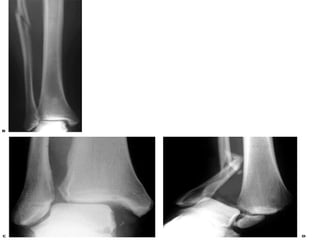

Maissoneuve Fracture

   Fracture of proximal

1/3 of fibula

   +/- medial malleolar

fracture

   Pronation-external

rotation mechanism

   Requires reduction

and stabilization of

syndesmosis